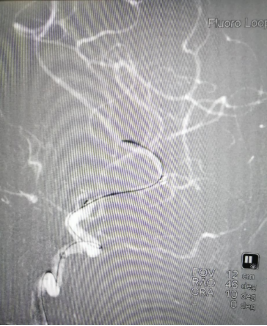

微导丝较顺利通过支架

微导管到位撤出微导丝

Transand微导丝到位撤出微导管

赛诺球囊扩张(1.5 mm×15 mm)

赛诺球囊扩张后狭窄有所改善但管壁不光滑